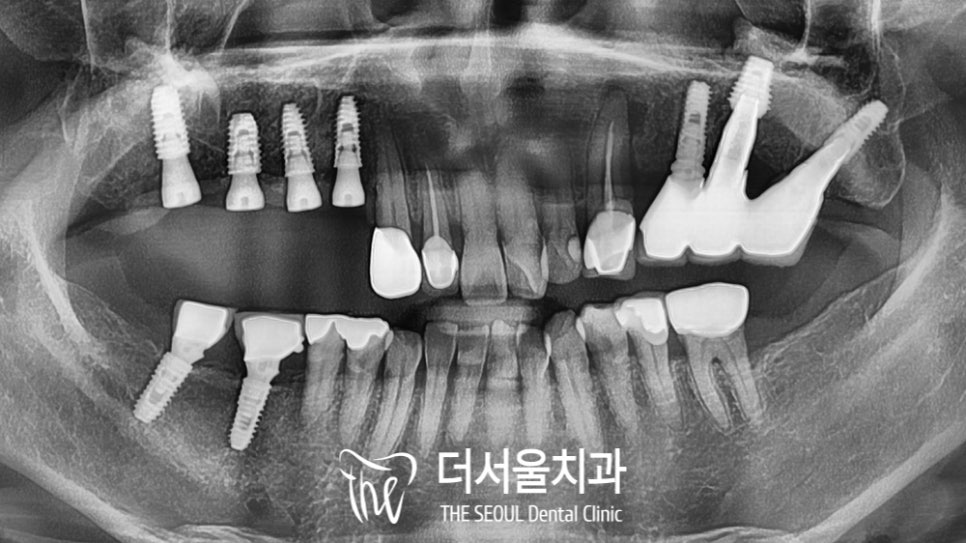

우선 오른쪽부터 치료를 시작하기로 했습니다.

이곳도 염증이 심한 상태였는데요.

발치를 진행하는 동시에 주변으로 퍼져 있는

염증들을 깨끗하게 제거하는 과정을 거쳤습니다.

이후 소독을 꼼꼼하게 한 뒤,

임플란트 부작용 이 생기지 않게끔!

정밀 진단을 토대로 식립 방향을 결정했습니다.

『자 이제 계산된 위치에

픽스처를 심어드릴 차례죠?』

4개의 고정체를 심었는데요.

잇몸뼈가 모자란 곳은

골이식을 동반하여 진행했습니다.

다행히 초기 고정력이 어느 정도 나왔기 때문에

예후가 나쁘지 않을 것으로 판단이 되었습니다.

골유착을 지켜본 뒤 최종 보철을 제작하기로 했죠.